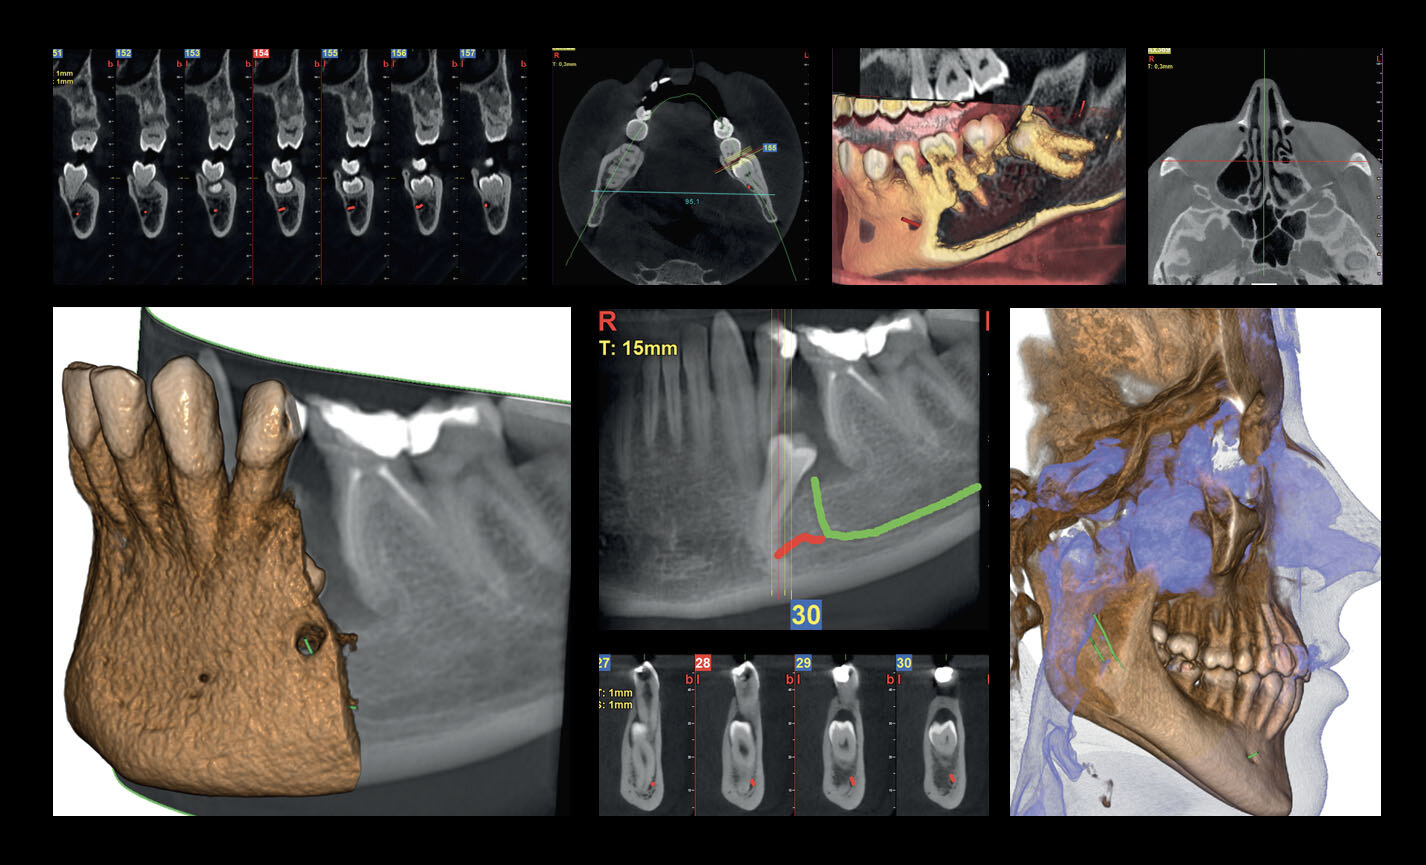

Des FOV de 10 cm de diamètre sont nécessaires pour l’étude des troisièmes molaires incluses car, chez un adulte de taille moyenne, la distance entre les troisièmes molaires de droite et de gauche, en incluant leurs racines respectives, le processus alvéolaire et l’os avoisinant, est d’au moins 9 cm. Les champs de vision réduits sont utiles en cas d’analyse de dents incluses ou surnuméraires, pour limiter la dose à la seule région d’intérêt. En effet, pour une planification correcte du traitement, il est fondamental de déterminer la position réelle (vestibulaire ou palatine), possible uniquement avec une analyse 3D, même à très faible dose avec un protocole QuickScan. Le champ de vision complet 13 x 16 cm permet une évaluation minutieuse des voies aériennes supérieures, souvent utile pour compléter une investigation en vue d’un traitement orthodontique qui tienne compte des problématiques oto-rhino-laryngologiques.

Planification implantaire avancée

Définissez la position de l’implant directement sur le modèle 3D, combinez-le avec les données STL provenant de scanners intra-oraux, et déterminez le projet prothétique définitif. Avec les instruments de planification implantaire avancée, vous pourrez opérer en toute sécurité, grâce aux informations précises sur la quantité d’os et la distance par rapport aux structures anatomiques avoisinantes, comme le canal mandibulaire, en définissant une distance minimale de sécurité.

Analyses volumétriques

La fonction du logiciel de calcul du volume de soulèvement du sinus maxillaire permet de déterminer l’intervention à l’avance et d’opérer en toute sécurité. Il est en outre possible de tracer des lignes directement sur le modèle virtuel du patient en évaluant les rapports morphologiques sur le rendu 3D.

Évaluation des implants zygomatiques

Les volumes avec FOV 13 x 8 cm, ou 13 x 10 cm, représentent l’outil idéal pour la planification des implants zygomatiques. En effet, le diamètre de 13 cm est le seul qui permet d’inclure tout le zygoma dans le balayage, sans coupes.